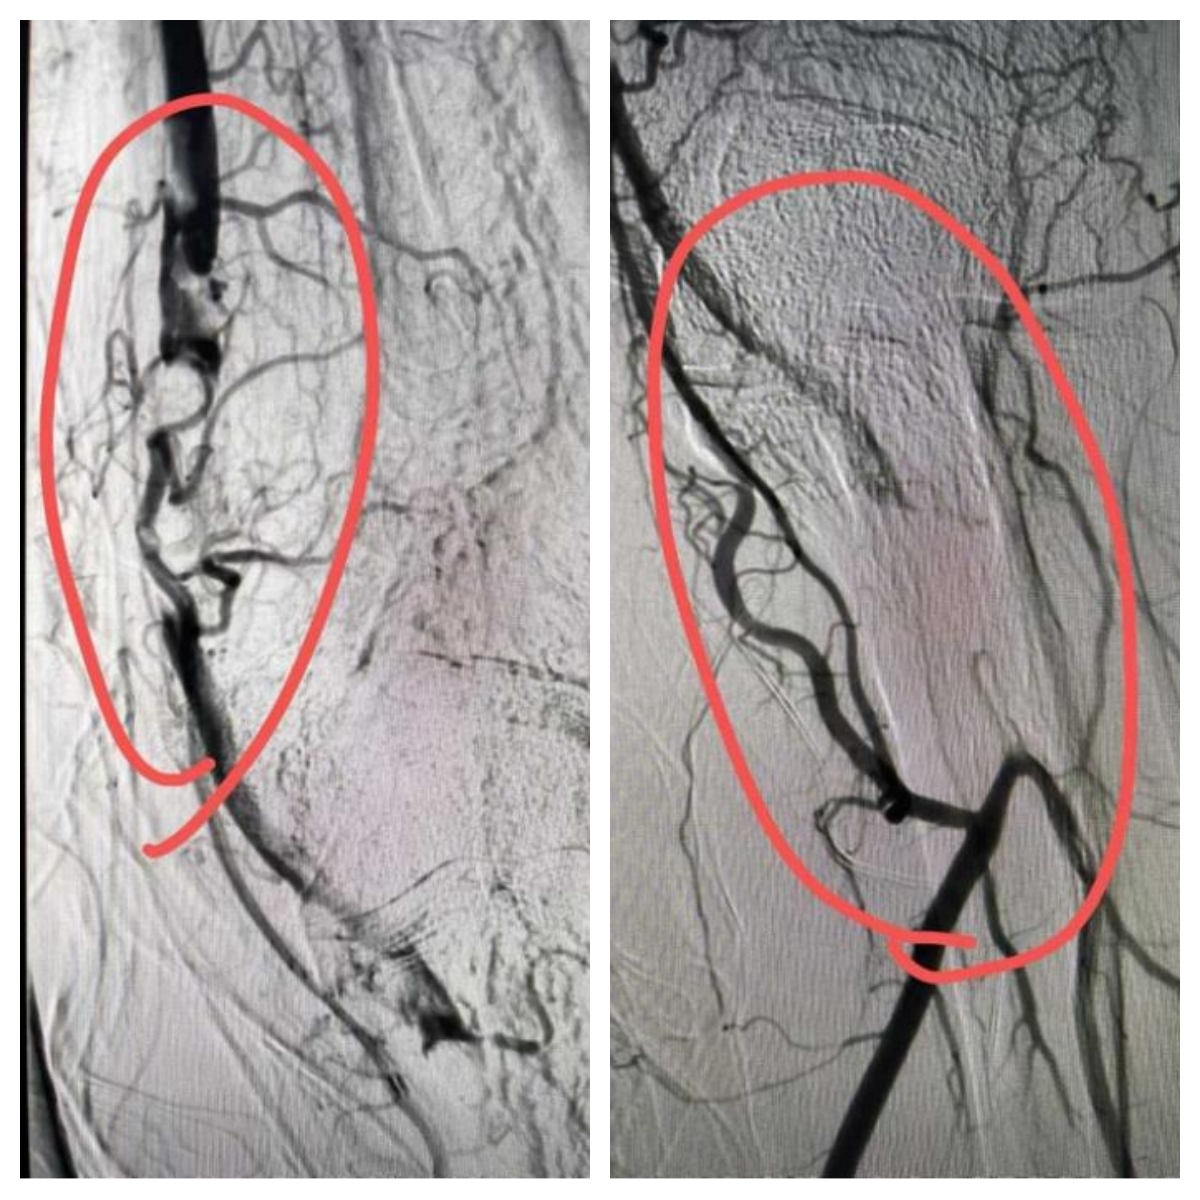

(血栓抽吸前)

(血栓抽吸中)

手术经右侧股动脉穿刺,将5F亲水涂层造影导管精准送至肱动脉近段。造影显示患者肱动脉血栓负荷较重,血流严重受阻,但已形成侧枝循环,为手术提供了有利条件。随后,团队实施机械血栓清除术,多次操作后血栓明显减少。为进一步改善血管通畅度,术中采用4.0mm×150mm非顺应性外周动脉血管球囊对病变段进行扩张。扩张后再次造影检查后显示,患者肱动脉病变部位扩张效果良好,血流恢复正常,手术顺利完成。